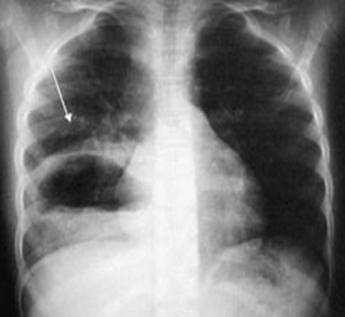

Derrame pericárdico severo da imagen en botellón en la radiografía de tórax. (ENAM EXTRA 2021)

(ENAM EXTRA 2022) (ENARM 2021)